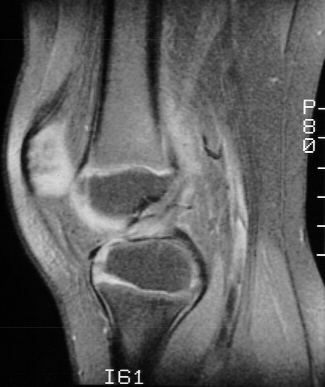

The patient was sent for physical therapy and an MRI to rule out ligament

or meniscal injury. MRI was read by radiologist as anterior cruciate ligament

tear and small medial meniscal tear

- MRI : 97% accurate compared to arthroscopy in diagnosing ACL tears

(ages 14-69, average age 33)

Less accurate in diagnosing tears in children